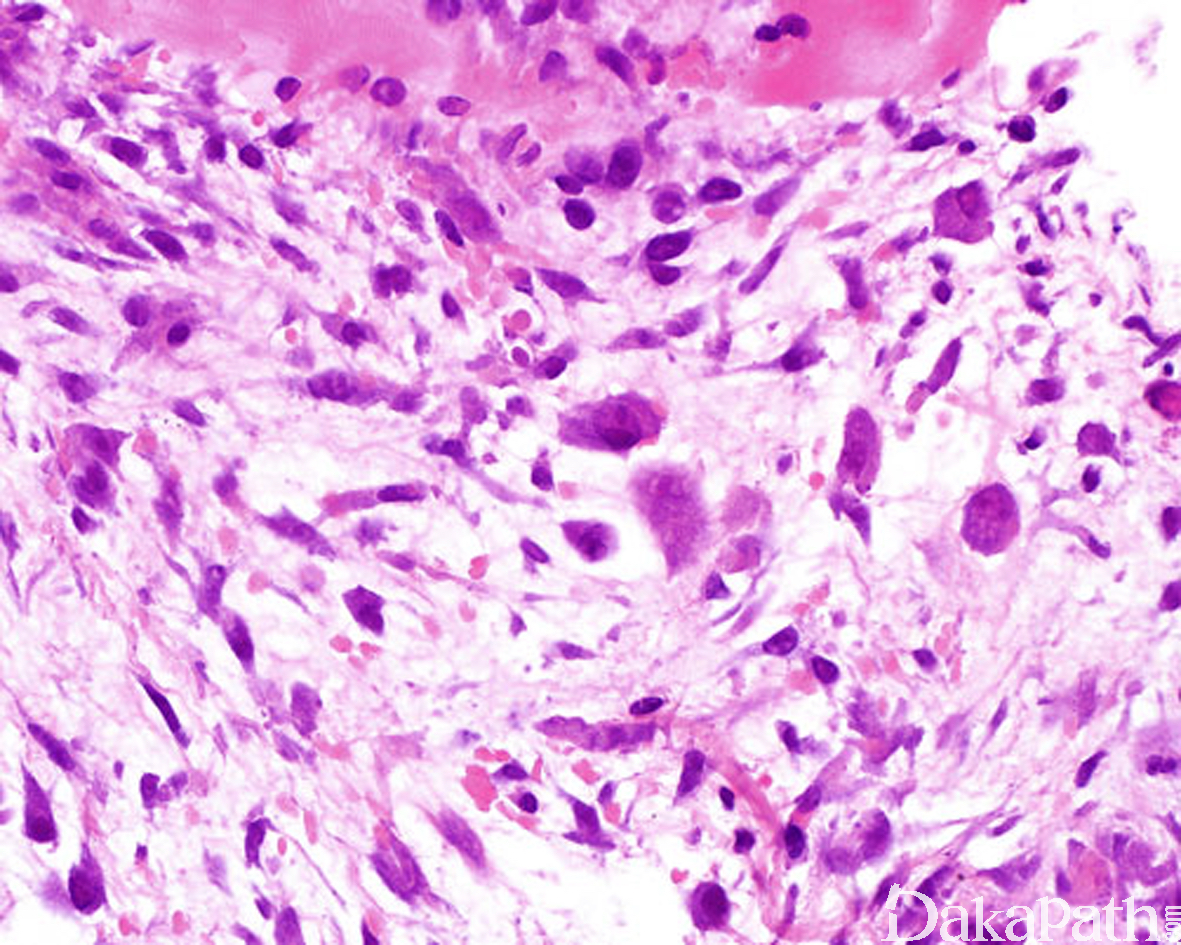

由大量增生的纤维母细胞、肌纤维母细胞、节细胞样细胞和形态上介于两者之间的过渡形细胞组成;

纤维母细胞、肌纤维母细胞呈梭形或胖梭形,也可呈蝌蚪状和不规则形,核膜厚,染色质呈空泡状,可见核仁,核分裂像多少不等,但无病理性核分裂;

节细胞样细胞体积较大,呈多边形或不规则形,胞质丰富,双染性至嗜碱性,核大,圆形或卵圆形,常偏向胞质一侧,核膜厚,可见 1 ~ 2 个深蓝色散在或成群分布于纤维母细胞或脂肪细胞之间,有些细胞核仁突出,呈紫色包涵体样,致细胞呈核枭眼样;

间质含有多少不等的黏液样物质和胶原纤维;

病变穿插于横纹肌纤维之间,在横切面上常形成“棋盘”样,不累及横纹肌纤维本身;